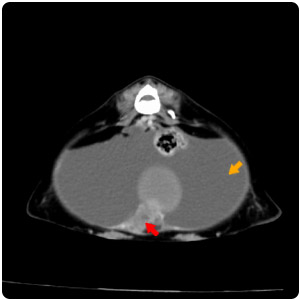

| Hernia |

脊椎旁腫塊(黃)、脾腫塊(紅) |